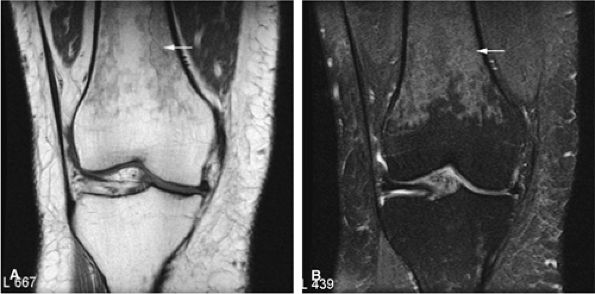

![]() |

FIGURE 14-7 ● Osteoid osteoma of the proximal femur. Coronal graphic illustration shows tumor nidus in red with surrounding sclerosis.

FIGURE 14-8 ● (A) Anteroposterior radiograph shows focal sclerosis of the medial tibial metaphysis (arrow). T1-weighted coronal (B) and sagittal (C) images reveal the osteoid osteoma nidus (straight arrows) and thickened cortex (curved arrow). (D) Scanning lens photomicrograph shows the nidus surrounded by sclerotic reactive bone. (E) High-power photomicrograph of the nidus demonstrates young neoplastic osteoid formation in an angiofibrotic background speckled with osteoblasts and giant cells.

On T1-weighted images, the nidus of the lesion demonstrates low to intermediate signal intensity (Fig. 14-8).

On T2-weighted images, the central nidus demonstrates moderate to increased signal intensity.41,42

Intracapsular osteoid osteomas of the hip usually cause a synovial inflammatory response and are associated with joint effusions and variable reactive marrow edema.43,44 Reactive sclerosis demonstrates low signal intensity on T1- and T2-weighted images. There may be extensive marrow edema associated with osteoid osteomas, and STIR or fat-suppressed T2-weighted fast spin-echo sequences can be used to screen for this reactive edema (Fig. 14-9).